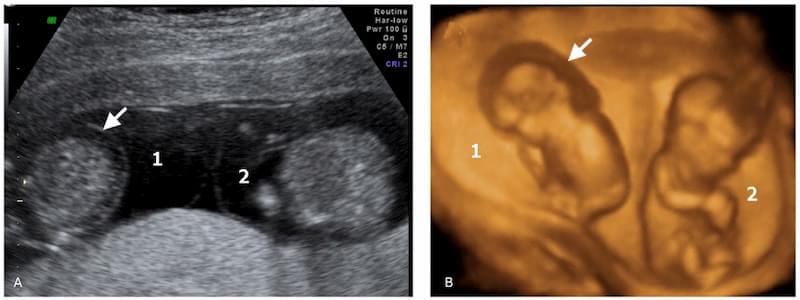

В первые 6-8 недель врач на УЗИ уже наверняка скажет тип близнецов (количество плаценты и амниотических пузырей). Это важные данные, которые нужно определить поскорее.

Плод развивается нормально в том случае, если у него есть собственный хорион и амнион (мешочек, в котором находится ребенок до рождения). Еще лучше для малыша, если он имеет и отдельную плаценту (неактуально для однояйцевых близнецов). В норме яйцеклетка начинает делиться в первые 3 суток после оплодотворения, тогда у каждого эмбриона образуется отдельный амниотический мешок с околоплодными водами.

Двуплодная беременность опасна, если запоздает начало деления яйцеклеток, вплоть до 13 суток. У таких плодов на двоих один общий хорион и амниотический мешок, они соприкасаются друг с другом. При неудачном стечении обстоятельств плоды сращиваются: зарождаются либо сиамские близнецы, либо дети имеют на двоих один орган (конечность).